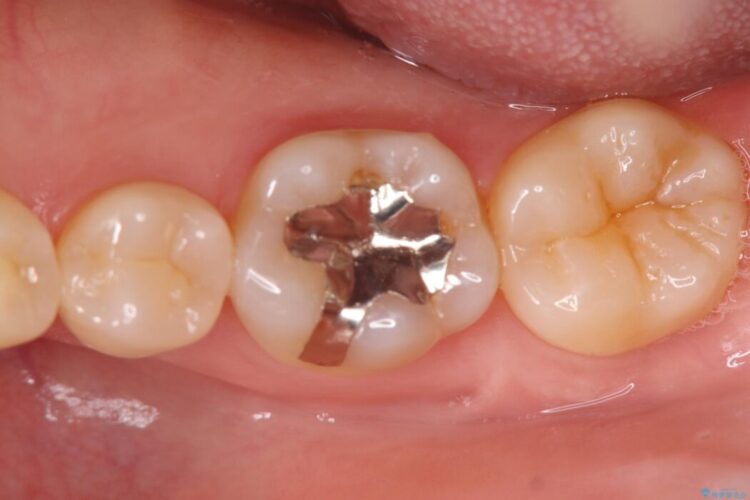

詰め物内部の虫歯治療、隠れた根管の発見

詰め物内部の虫歯治療、隠れた根管の発見 ビフォー 詰め物内部の虫歯治療、隠れた根管の発見 アフター

奥歯の詰め物が取れたとご来院された患者様です。